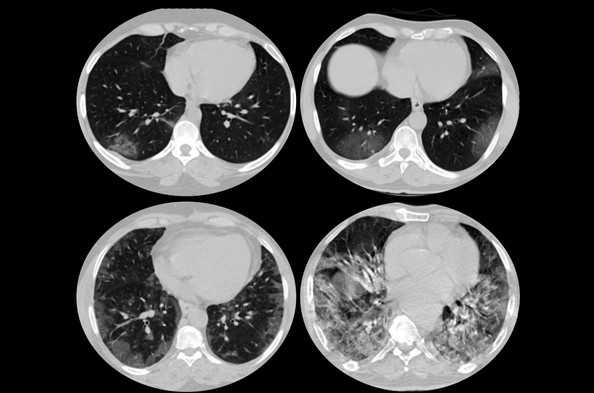

КТ грудной клетки (легкие, плевра, средостение и сердце)

В этом модуле e-Anatomy приведена нормальная КТ-анатомия грудной клетки (легкие, плевра, сердце, аорта, лимфатические узлы и другие соответствующие анатомические структуры).

Цель модуля - помочь радиологам в их ежедневной практике. Особое внимание уделено таким темам, как сегментарная анатомия легких; группы лимфатических узлов согласно Международной ассоциации по изучению рака легкого (IASLC) в классификации клинической стадии рака легкого; измерение размеров грудной аорты в планировании транскатетерной замены аортального клапана (TAVR) или в последующем наблюдении аневризмы грудной аорты. Модуль является средством изучения лучевой анатомии грудной клетки и рассчитан на студентов медицинских институтов, а также врачей, проходящих обучение в ординатуре по специальности «Радиология», «Пульмонология», «Онкология» или «Торакальная хирургия».

Компьютерная томография грудной клетки была проведена французским радиологом Антуаном Мишо (Antoine Micheau MD, Imaios) с помощью Siemens Somatom Definition Edge. Пациент - мужчина, 43 года, без патологических изменений. Технические особенности:

| Collimation: 128 x 0.6 mm | Tube settings: 100 kV, 70 eff. mAs |

| Pitch: 1.7 | DLP: 172 mGy cm |

| Scan time: 2.5 s | CTDIvol: 2.77 mGy |

| Scan length: 580 mm | Eff. dose: 2.49 mSv |

| Rotation time: 0.28 s | Heart rate: 64 bpm |

Осуществлялось введение йодсодержащего контрастного вещества (Omnipaque [Iohexol] 350 мг йода/мл). КТ проводилась с ЭКГ-синхронизацией.

Здесь представлены изображения (паренхиматозное и средостенное окно) с многоплановыми реконструкциями (MPR) во фронтальной (корональной) и сагиттальной плоскостях.